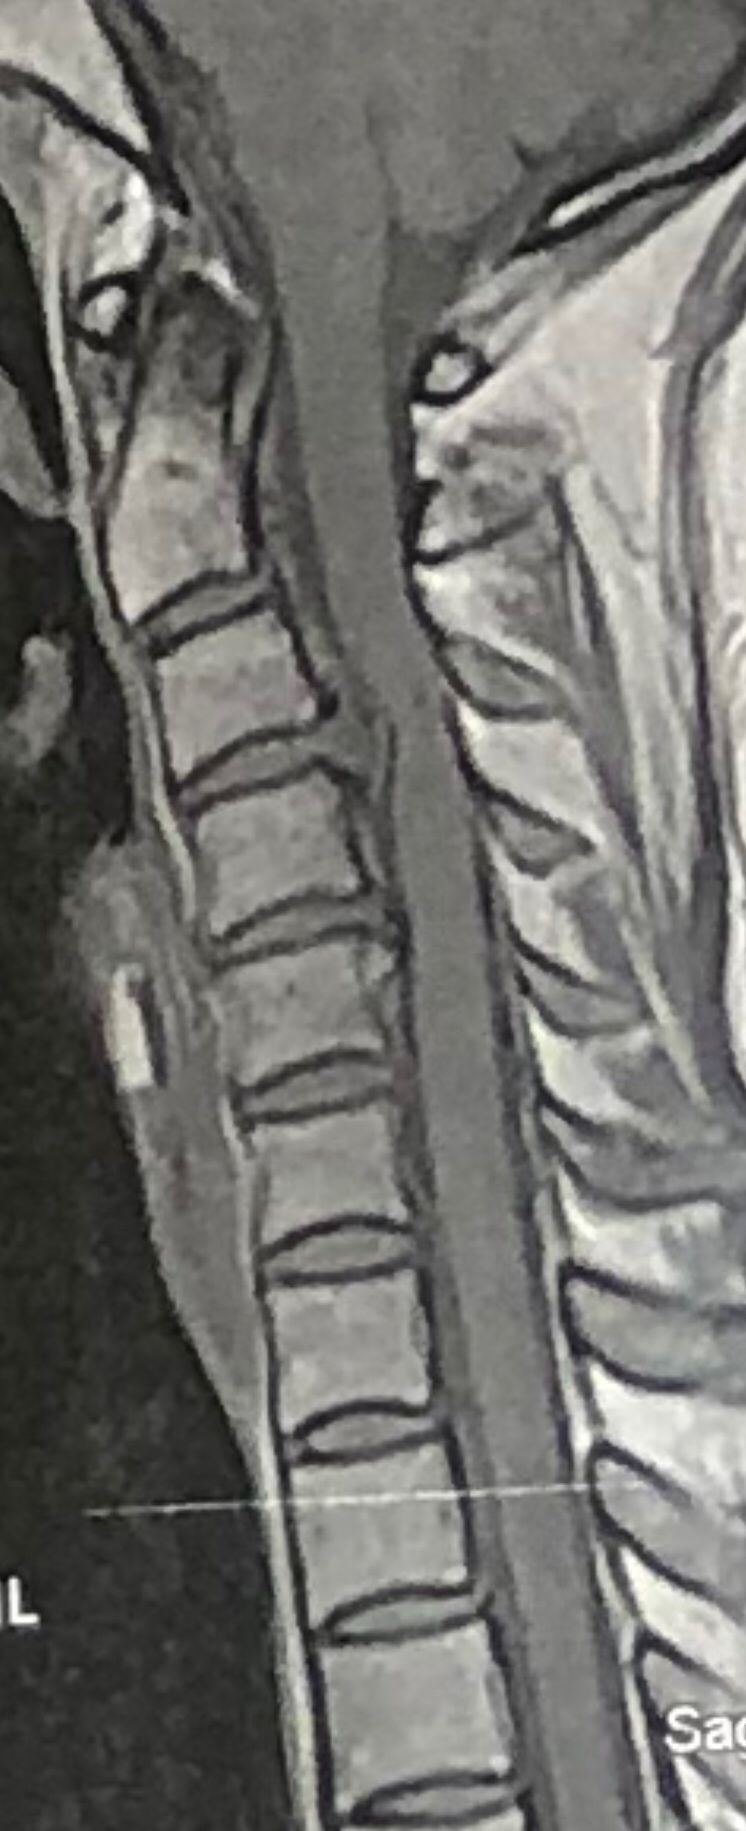

30 year old patient of mine with R. IVF disc extrusion of C 5-6 with R upper extremity pain and numbness without neurological deficit was suggested to have urgent surgery

in his EMG. NCV didn’t have any active axonal loss

got 20 sessions of chiropractic care in one month by me mainly using decompression and C0-C1 prone drop manipulation and 3 sessions of mild adjustment to segments above disc herniation. No direct adjustment to the involved disc extrusion

After treatment:

reduction of R. IVFdisc extrusion by more than 50%.

90% improvement in patient’s signs and symptoms and preventing of unnecessary expensive surgery

following one month of cervical chiropractic spinal treatments